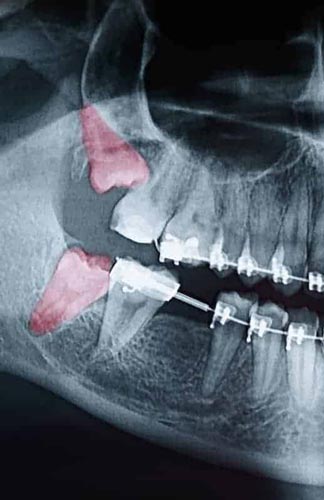

Most people’s mouths only have enough room for 28 teeth. When your wisdom teeth start to come in, that’s four additional teeth trying to cram their way in. In the majority of situations, this creates a litany of problems, including crowding, soreness, risk of infection, and the need for extraction. Since your wisdom teeth are the last teeth to erupt in through your gums, they come to the party a little late. All your other teeth have settled into their places. With x-rays and inspections, we can determine if your wisdom teeth are impacted and need to be removed. Since wisdom teeth rarely come in straight and even with the rest of your smile, we have years of experience analyzing them and extracting them at Oral & Maxillofacial Surgery Associates. Wisdom teeth can also come in sideways, causing even more issues for you if we don’t act. If you or your child is approaching the age of 18, it’s crucial to bring them in for an examination for their wisdom teeth. Call us today to schedule your appointment for a wisdom teeth analysis or extraction in the Flowood and Madison area.

Though some patients may not require the removal of their wisdom teeth, most often, it’s needed to protect your overall oral health. Wisdom teeth can begin to grow in sideways, only partially erupt, or even get stuck beneath the gum and bone. Known as impacted teeth, those that get stuck may resort to shifting position as the try to find a pathway for eruption. When wisdom teeth don’t erupt through the gumline properly, they can create severe problems for the patient, including:

To evaluate the state of your wisdom teeth, we’ll first do a thorough examination and take x-rays of your mouth. This will help us determine if your wisdom teeth pose a current or future threat to your oral health. Early detection of issues results in better outcomes for our patients, so we recommend the first evaluation be completed in a patient’s mid-teenage years.